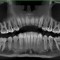

L’Unità Operativa di Radiologia Odontoiatrica, ubicata presso il Dipartimento, è dotata di apparecchiature all’avanguardia nella diagnostica odontostomatologica e del massiccio-facciale. In particolare è presente un’apparecchiatura TC Cone Beam di ultima generazione che consente l’acquisizione volumetrica ad alta definizione ed a bassissima dose dell’intero volume cranio-facciale comprese le articolazioni temporo- mandibolari e le prime vertebre cervicali. Tale esame oggi trova larga applicazione nel campo della diagnostica odontoiatrica e del massiccio facciale, come lo studio pre e post-implantare, la valutazione di elementi dentali inclusi, lo studio di lesioni odontogene e non odontogene, la traumatologia cranio-facciale ed anche la valutazione dei seni paranasali, dell’orecchio e delle articolazioni temporo-mandibolari. Grazie all’acquisizione volumetrica ed alla bassa dose di radiazioni tale metodica è oggi indicata anche nella pianificazione del trattamento ortodontico. Nell’Unità Operativa è inoltre presente l’Orthophos Plus della Sirona Dental System che consente di effettuare esami radiografici standard digitali delle arcate dentarie, dei seni paranasali e delle articolazioni temporomandibolari ed inoltre teleradiografie nelle proiezioni latero-laterale ed antero-posteriore per studio ortodontico. L’Unità Operativa è collegata in rete con i vari reparti della clinica per una rapida consultazione degli esami radiologici.

- OPT